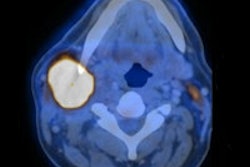

Per-capita effective doses in Europe. All images courtesy of Ritva Bly.As for modalities, the highest average contribution is from CT, at a mean 57% of all exposures across Europe. Plain radiography counted for 19%, fluoroscopy 17%, and interventional radiology 7.5%, but those levels varied widely between countries. In Denmark and Luxembourg, more than 80% of the dose was contributed from CT, she said, while other countries, like the Czech Republic, had less than 40% of their dose coming from CT. CT procedure numbers were relatively low, accounting for 16% of all procedures at most, Bly said.

The mean effective doses varied significantly, Bly said. Chest and thorax doses ranged from 0.014 mSv to 0.26 mSv, but head CT had a smaller range, 3 mSv to 4 mSv, and percutaneous coronary angioplasty (PCTA) ranged only from 6 mSv to 8 mSv, she said. The nuclear medicine contribution represented only 0.2% of the total dose at a mean of 0.36 mSv. Heart and bone exams composed 40% and 36% of all exams, respectively.